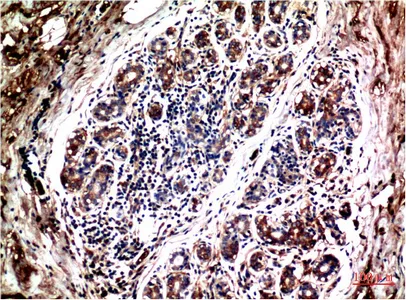

Galectin-3(8D7)Mouse Monoclonal Antibody

Cat: AMM11273

Size1:50μl Price1:$128

Size2:100μl Price2:$230

Size3:500μl Price3:$980